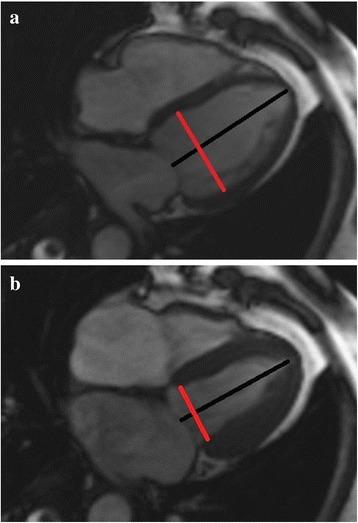

Type 2 diabetes mellitus (DM2) may induce epicardial coronary artery diseases and left ventricular myocardial damaging as well. Left ventricular dysfunction was found in DM2. In this research, we compared the left ventricular dysfunction of coronary artery disease (CAD) patients with and without type 2 diabetes mellitus as well as normal controls using the volume-time curve of cardiac magnetic resonance (CMR).

METHODS

Sixty-one CAD patients (28 with DM2 and 33 without DM2) and 18 normal individuals were enrolled in this study. Left ventricular function parameters, including the end-diastolic and end-systolic volumes (EDV, ESV), stroke volume (SV) and ejection fraction (EF), and morphologic dimension parameters (end diastolic and systolic diameter (EDD and ESD), were measured and compared. Volume-time curve parameters, including the peak ejection rate (PER), peak ejection time (PET), peak filling rate (PFR), peak filling time from ES (PFT), peak ejection rate normalized to EDV (PER/EDV), and peak filling rate normalized to EDV (PFR/EDV), were derived automatically and compared.

2型糖尿病(DM2)可能诱发心外膜冠状动脉疾病以及左心室心肌损伤。在DM2患者中发现了左心室功能障碍。在本研究中,我们使用心脏磁共振成像(CMR)的容积-时间曲线,比较了合并和不合并2型糖尿病的冠心病(CAD)患者以及正常对照者的左心室功能障碍情况。

方法

本研究纳入了61例CAD患者(28例合并DM2,33例不合并DM2)和18名正常个体。测量并比较左心室功能参数,包括舒张末期和收缩末期容积(EDV、ESV)、每搏输出量(SV)和射血分数(EF),以及形态学尺寸参数(舒张末期和收缩末期直径(EDD和ESD))。自动得出并比较容积-时间曲线参数,包括峰值射血率(PER)、峰值射血时间(PET)、峰值充盈率(PFR)、从收缩末期开始的峰值充盈时间(PFT)、以EDV标准化的峰值射血率(PER/EDV)以及以EDV标准化的峰值充盈率(PFR/EDV)。